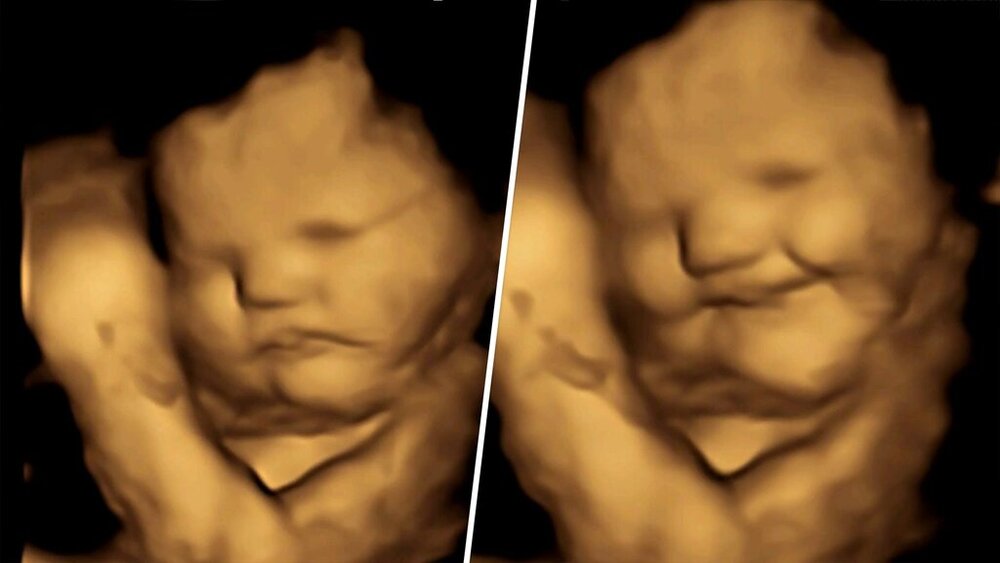

در این مطالعه، محققان به ۱۰۰ زن باردار یک کپسول حاوی تقریباً ۴۰۰ میلیگرم هویج و یا پودر کلم پیچ دادند و از آنان خواستند تا حدود یک ساعت قبل از سونوگرافی ۴ بعدی، هیچ غذا یا نوشیدنی طعمدار دیگری مصرف نکنند.

۲۰ دقیقه پس از اینکه مادران کپسول هویج یا کلم پیچ را خوردند، محققان آزمایشگاه تحقیقات جنین و نوزاد دانشگاه دورهام در بریتانیا کار تصویربرداری را شروع کردند و در کمال تعجب با واکنش و میمیکهایی دیدنی از صورت جنینها روبرو شدند.

جنینهایی که مادرانشان کپسول هویج خورده بودند، واکنشهای خنده بیشتری نشان دادند، در حالی که آنهایی که طعم کلم پیچ را چشیدند، واکنشهایی شبیه به گریه نشان دادند.

واکنشهای صورت این بچههای بانمک با گروه کنترلی که در معرض هیچ کدام از طعمها قرار نگرفتند مقایسه شد.